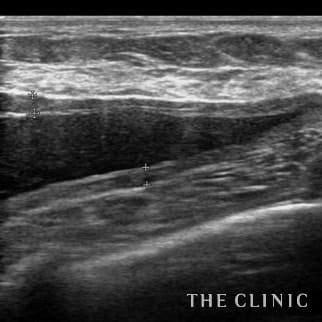

Breast-hip Photo Gallary / No.698

50歳 女性 アクアフィリング(アクアリフト)豊胸のお悩みのアクアフィリング(アクアリフト)豊胸除去

10日前に他院でアクアフィリング豊胸(片胸100ccづつ)を行いましたが、安全性に不安を感じたこと、形や硬さも気に入らないため除去を希望されました。形も悪く、しこりのようになっていました。 エコーをすると乳腺下にアクアフィリングが注入されていましたが、一部は大胸筋内に広がっていました。(写真は乳腺科に見られた大きな塊、黒い部分です。) 処置はエコー下に生理食塩水で溶解して吸引除去でき、無事、形も柔らかさも元に戻りました。治療の概要 アクアフィリング除去+コンデンスリッチ豊胸:乳腺用エコーを用いて、バスト内の状態を確認。その後、生理食塩水でアクアフィリングを溶解する。溶解仕切れない場合には、注射器で吸い出し除去。アクアフィリング の除去後、バストの皮下にコンデンスリッチファット(老化細胞や不純物を取り除いて濃縮させた自己脂肪)を注入。 施術費用 アクアフィリング 除去(会員料金):¥600,000(税込¥660,000)/溶解1部位

コンデンスリッチ豊胸(モニター価格):¥880,000〜(税込¥968,000〜)